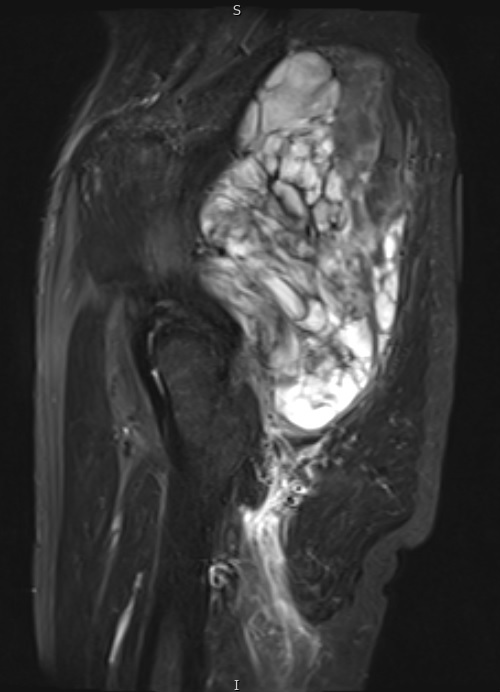

Fig. 6 STIR MR image demonstrates a large mass in the gluteal region with some enhancing tissue posterior to the trochanteric area which may reflect reactive edema.

Fig. 7 & 8 Magnetic Resonance Image shows a large heterogeneous mass in the right thigh with low intensity signal on Axial (Fig. 7) and Coronal (Fig. 8) T1-weighted images admixed with high signal areas. The high signal areas represent low grade fatty tissue and low signal the dedifferentiated areas. Higher intensity signal is visible compatible with hemorrhage or necrotic tissue.

Fig. 9 Coronal fat suppressed T1-weigthed MR image demonstrates a large heterogeneous mass in the anterior compartment of the thigh with some areas suppressed corresponding with fatty areas within the tumor. Central hyper enhanced areas compatible with hemorrhage or necrosis.

Fig. 10 Axial T2 weighted MR image demonstrates a large well encapsulated heterogeneous mass with multiple thick internal trabeculations located in the anterior compartment of the thigh.